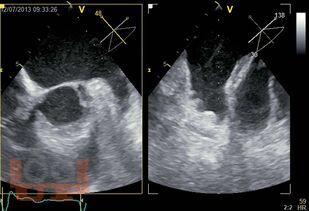

Книга посвящена методу чреспищеводной эхокардиографии, в основном многоплановой чреспищеводной эхокардиографии, которая в настоящее время является наиболее распространенным вариантом чреспищеводного исследования. Уделено внимание вопросам безопасного использования этого высокоинформативного метода. Подробно анализируются возможные осложнения и меры предосторожности при выполнении исследования. Приведены основные доступы и позиции при многоплановой чреспищеводной эхокардиографии и способы их выведения, терминология доступов и позиций, а также манипуляций датчиком. Основные ультразвуковые позиции сопоставлены с топографическими сечениями на анатомической модели чреспищеводного симулятора. Описаны сердечные структуры в норме и при различных патологических состояниях. Представлены возможности и ограничения метода, его клиническое значение.